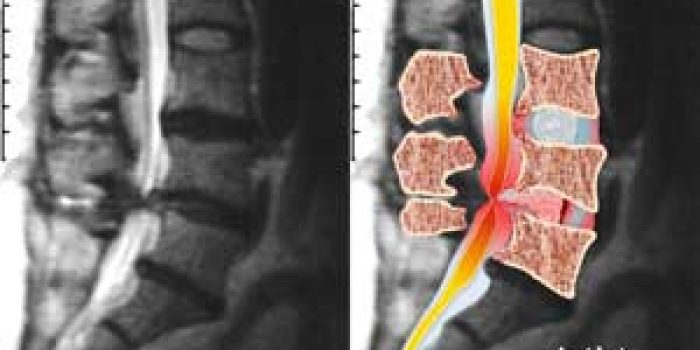

تنگی کانال نخاع در حقیقت اصطلاحی است که برای بیان باریک شدن بخش تحتانی مسیر عبور نخاع (کانال نخاع) در ستون فقرات به کار می رود.

کانال نخاع وظیفه حفاظت از نخاع و ریشه های عصبی را به عهده دارد. در صورتی که کانال نخاع از میزان خاصی در هر یک از محل های نخاع گردنی ، پشتی یا کمری باریک تر باشد (بسته به میزان باریکی که ایجاد شده) می تواند برای بیمار مشکل ساز باشد. این تنگی می تواند نسبی و یا کامل باشد.

اگر چه مواردی از تنگی کانال نخاع از بدو تولد وجود دارد، اما اغلب مبتلایان در سنین بالای ۵۰ سال هستند و بر اثر آسیب و پیر شدن ستون فقرات به این بیماری مبتلا شده اند.بسیاری از این افراد بدون علامت هستند، تا اینکه علت های دیگر باعث فشار بیشتر بر نخاع شده و تنگی را تشدید کنند.

در صورتی که این باریکی نخاع باعثآزردگی طناب نخاعی یا ریشه های آن گردد، باید به فکر حل این مشکل باشیم.